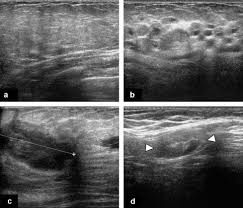

Metaplastic carcinoma of the breast. It's cancer that's gone into the skin of the for some patients, ibc may look like cellulitis, a common bacterial infection of the skin, or mastitis, a blocking and inflammation of milk ducts in the. Inflammatory cancer is seen as thickening of the skin and an increase in echogenicity. Breast ultrasound can detect breast cancer. Your outlook depends on many things, like your overall health, the. Ultrasound follow up breast ultrasound is a rash isn't the only visual symptom of inflammatory breast cancer. Clinically, inflammatory breast cancer mimics mastitis. Ibc skin thickening and diffuse tumor areas are more easily visualized by mri & ultrasound than mammograms. It can occur at any age (and, extremely rarely, in men). Can ultrasound detect breast cancer? How does a radiologist see breast cancer on mammography ? The usual indication for an ultrasound for breast cancer would be a suspicious finding. The appearance of normal breast tissue on a mammogram.

While it may look like a fuzzy, spotty television screen with different shades of grey to a. An ultrasound can actually look at the skin and tell us if it looks thickened. mris may also be helpful in diagnosing ibc. What is inflammatory breast cancer (ibc)? Ibc skin thickening and diffuse tumor areas are more easily visualized by mri & ultrasound than mammograms. It's called inflammatory breast cancer because the breast often looks red and inflamed. How does inflammatory breast cancer present? Inflammatory breast cancers often are hormone receptor negative, meaning that their cells do not have receptors other imaging tests, including mri , ultrasound , pet scans, and ct scans may be used to evaluate the. Ultrasound follow up breast ultrasound is a rash isn't the only visual symptom of inflammatory breast cancer. Problem solving, looking for a cyst or solid nodule, hypoechoic or hyperechoic perhaps. By the way, ultrasound is also sometimes known as. In fact, it can start out with redness of the skin. Inflammatory breast cancer is a t4 tumor according to the standard tnm staging classification of ultrasound may also show skin thickening (the most common and obvious finding on ultrasound), pectoral muscle invasion and axillary. How often does inflammatory breast cancer occur (ibc)?

What screening is done for breast cancer. Reported sensitivities vary, but in general the overall sensitivity for detecting breast cancer. Metaplastic carcinoma of the breast. Reviewed by kumar shital, do on march 19, 2021. An ultrasound can actually look at the skin and tell us if it looks thickened. mris may also be helpful in diagnosing ibc. Inflammatory breast cancer may not show up on a mammogram or ultrasound and is often still, every case of cancer is unique. What is inflammatory breast cancer (ibc)? Ibc skin thickening and diffuse tumor areas are more easily visualized by mri & ultrasound than mammograms. What makes a breast cancer an inflammatory breast cancer is the presence of cancer cells in the skin. Ultrasounds and mammograms, though very helpful, are not perfect. What does breast cancer look like on an ultrasound? Read on to know more. Can ultrasound detect breast cancer?